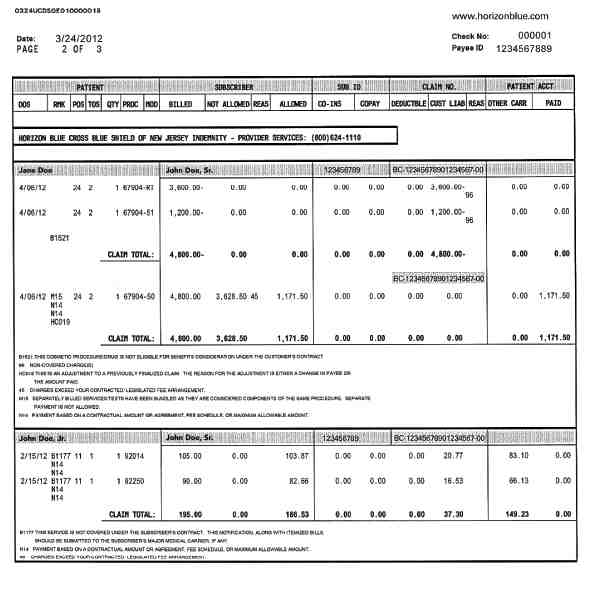

Does insurance cover full dental implants?

Basic dental insurance policies do not usually cover a dental implant procedure. You will need to examine the coverage of the cosmetic dental procedure, which covers part of the dental implants. This may interest you : Dental Implant Options. Your dental implant insurance coverage could cover 50% of the cost, which means that your insurance covers half of the procedure.